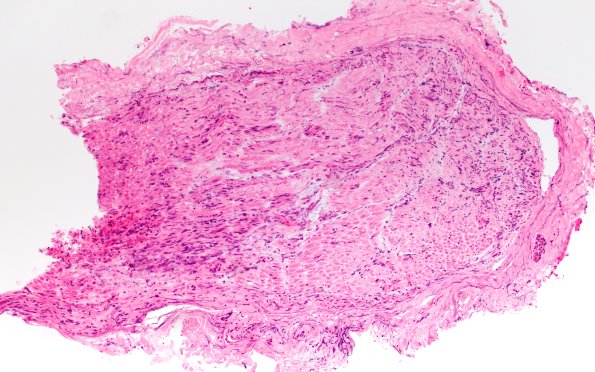

Washington University Experience | PERIPHERAL NEUROPATHY | 19 TRAUMATIC INJURIES | 12A1 Neuroma (Case 12) H&E 10X

Case 12 History ---- The patient is a 43-year-old man presenting with persistent pain following a left brachial plexus injury secondary to a gunshot wound, and electromyography showing a severe, diffuse left brachial plexopathy (likely postganglionic). Operative procedure: Biopsy of stump of posterior interosseous nerve. ---- 12A1,2 H&E-stained sections of the C5 nerve root biopsy show a nerve with focal areas of necrosis. (H&E)